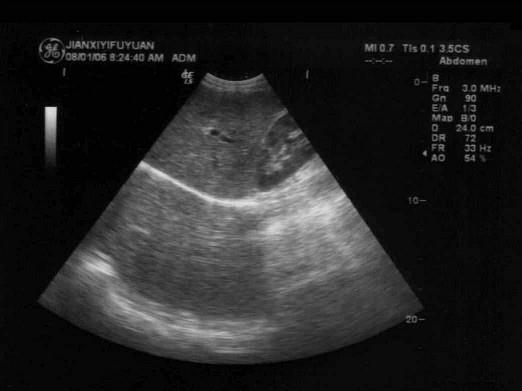

问题 右肝肋缘下向上扫查时常可见到镜面伪像,下列哪项是错误的?(?)

选项 A.正常肝脏:膈下为肝脏实像,膈上为肝脏虚像 B.肝内肿瘤:膈下、膈上各有一个对称的肿瘤,前者为实像,后者是伪像 C.肝内囊肿:膈下、膈上各有一个对称性肿瘤,前者为实像,后者是伪像 D.右侧胸腔积液时,以上镜面伪像更明显 E.右侧胸腔积液时,以上镜面伪像消失

答案 E